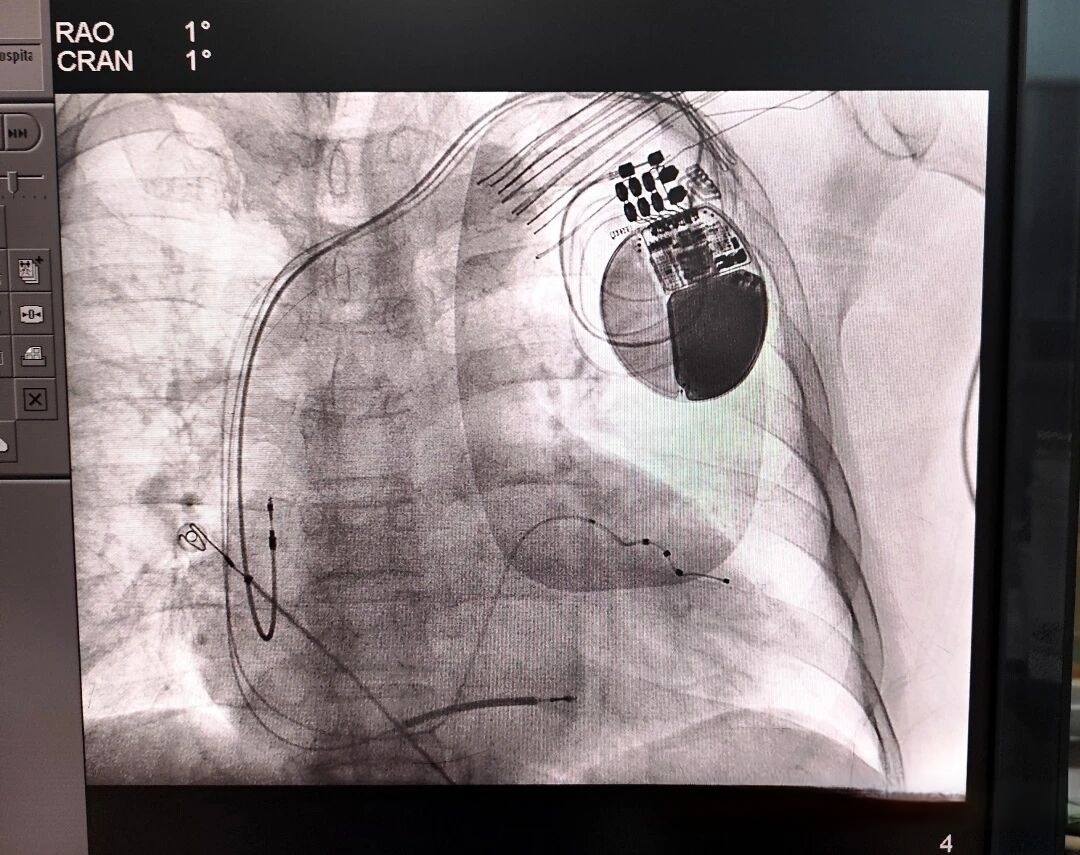

术中影像。